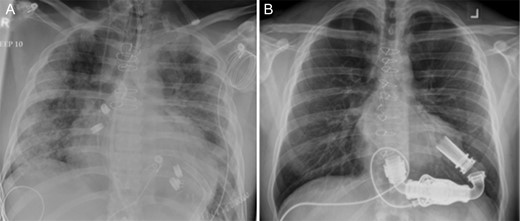

The HeartMate II LVAD was implanted in the usual fashion. Chest radiographs on admission and following implantation of LVAD are shown in Fig. 1. LVAD core pathology revealed cardiomyocyte hypertrophy, patchy myocyte death and histiocytic inflammatory reaction consistent with AAS induced heart failure [1, 3]. Postoperatively, he made gradual and steady improvement and was discharged home on postoperative day (POD) 34. He was connected with addictions counseling, rehabilitation and support to which he was compliant with. He was also maintained on aggressive medical therapy for heart failure including beta-blockers, afterload reduction with an angiotensin-converting enzyme inhibitor (ACEi), an angiotensin II receptor blocker (ARB) as well as aldosterone antagonists.

Chest radiographs (A) on admission, and (B) following implantation of a HeartMate II Left Ventricular Assist Device.